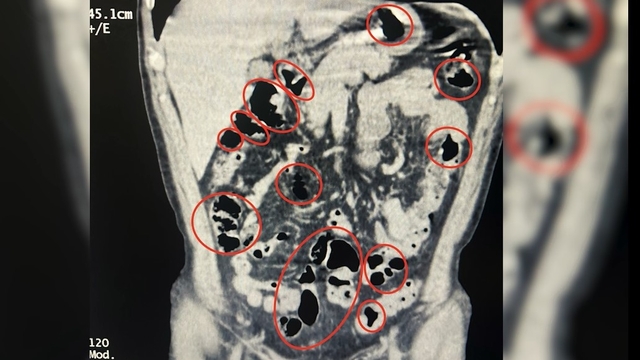

İl Emniyet Müdürlüğü Narkotik Suçlarla Mücadele Şube Müdürlüğü ile İstihbarat Şube Müdürlüğü ekiplerinin çalışması sonucu Tatvan ilçe girişinde durdurulan bir yolcu otobüsünde seyahat eden yabancı uyruklu 2 kişinin üzerinde arama yapıldı. Aramalarda şüphelilerin üzerinde 36 kapsül içerisinde uyuşturucu ele geçirildi. Tatvan Devlet Hastanesi’ne götürülen şüphelilerin burada yapılan röntgen ve tomografi incelemelerinde de mide ve bağırsaklarında yabancı cisimler tespit edildi. Tıbbi müdahale sonucu şüphelilerin yuttuğu 14 kapsül çıkarıldı. Toplam 50 kapsül halinde 385 gram metamfetamin ele geçirilen 2 şüpheli gözaltına alındı.